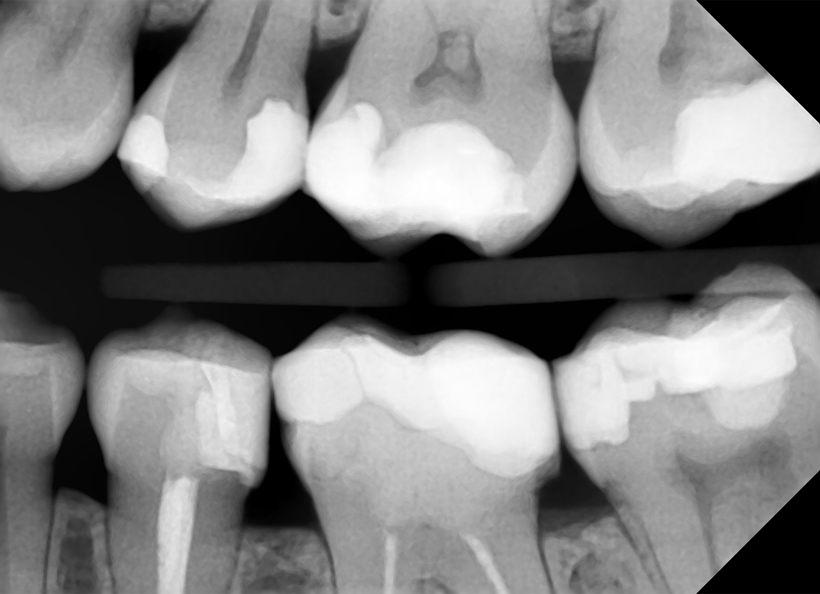

Radiografia digitală bitewing (muşcată) este o radiografie ce oferă informaţii precise (la fel ca şi radiografia retroalveolară) pe o zonă limitată a cavităţii bucale. Pe această radiografie medicul stomatolog poate vedea coroanele dinţilor, atât a dinţilor de pe maxilar, cât şi de pe mandibulă, cât şi rădăcina acestora. Este indicată în cazul cariilor interdentare, retracţiilor ososase, pungilor parodontale, etc.